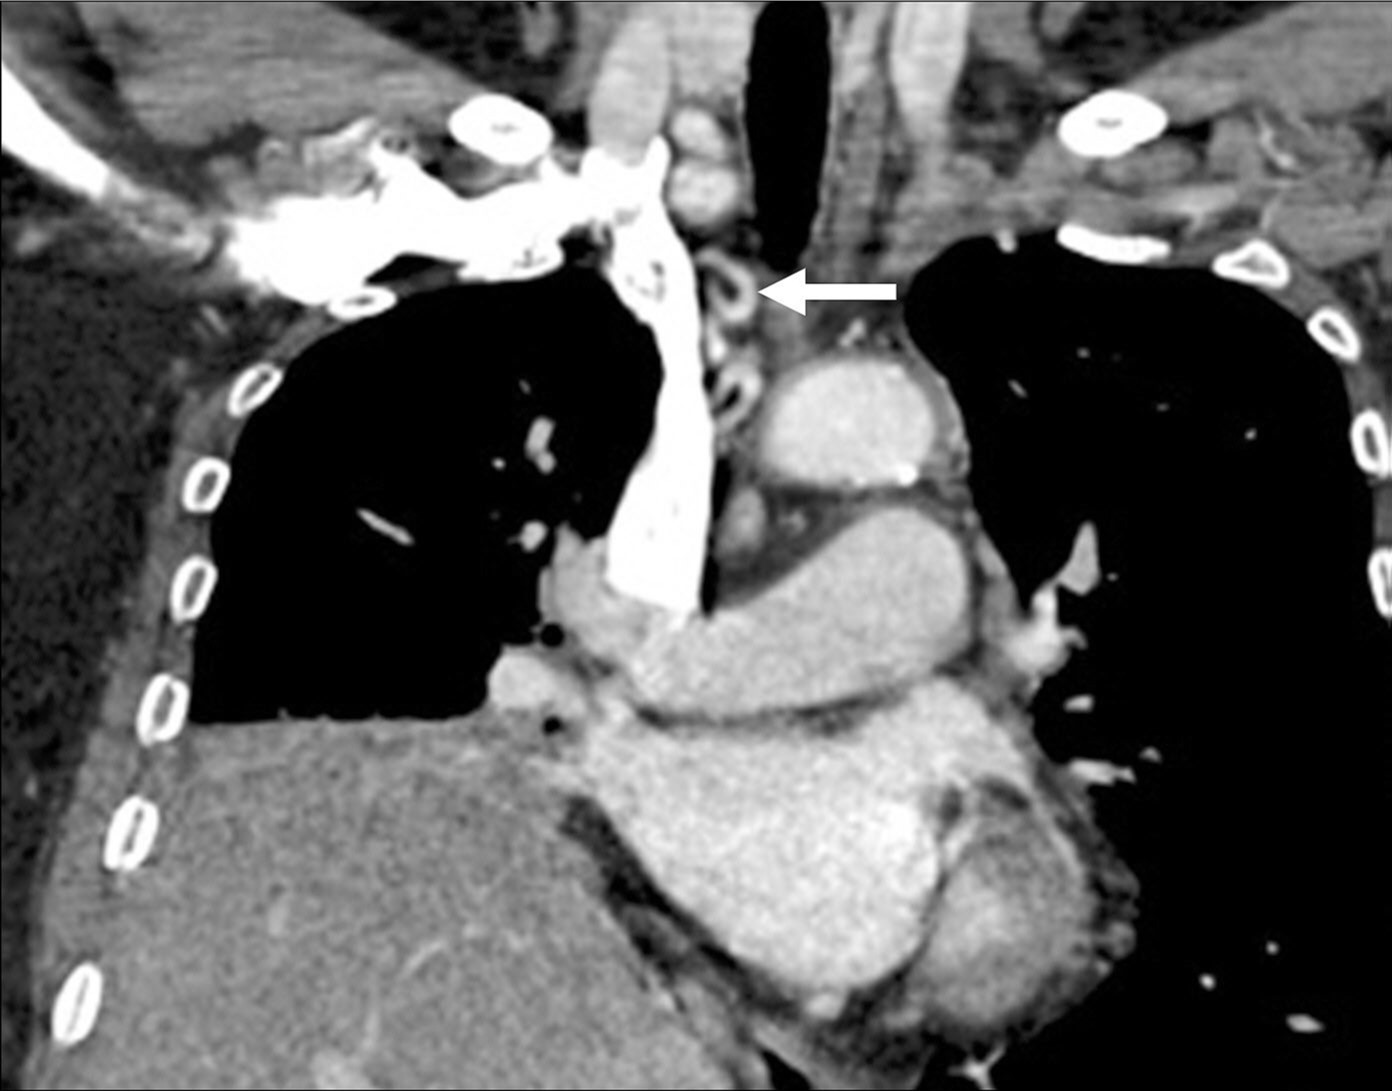

Fig. 4.

Fig. 4. Selective angiogram of the right inferior phrenic artery shows arterial hypertrophy, hypervascular parenchymal staining in the right lower lung field, and shunting to pulmonary circulation (arrow).